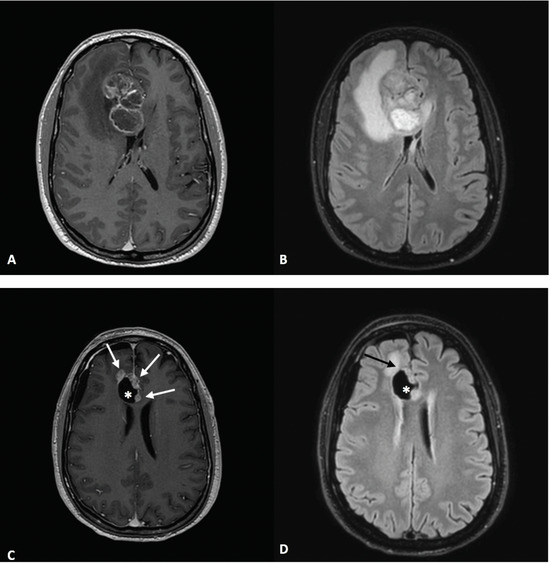

2. Case Report